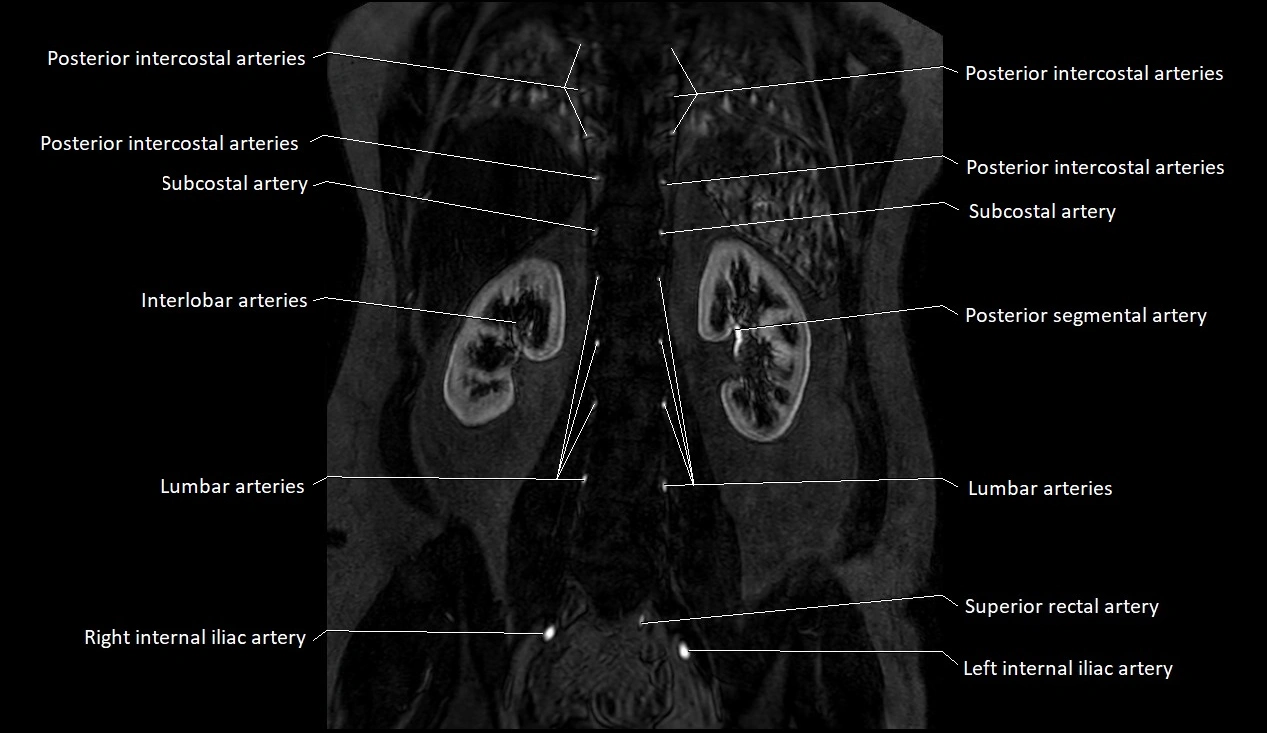

MRA (Magnetic Resonance Angiography):

• Contrast-enhanced MRA provides high-resolution imaging of the aorta and its branches

• Allows 3D reconstruction of visceral, parietal, and terminal branches

• Excellent for evaluating aneurysm size, dissection flap, stenosis, or preoperative planning

• Non-invasive alternative to conventional angiography

MRI images

image